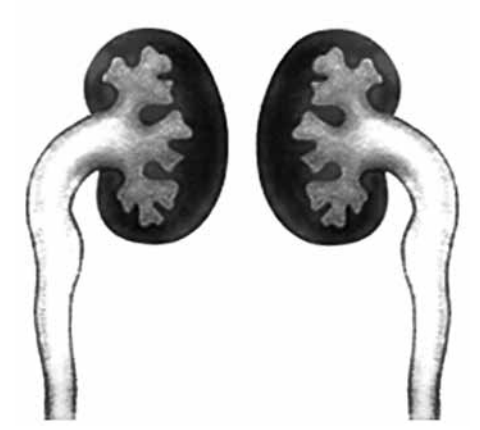

Criança de 2 anos, sexo feminino, apresenta infecção

do trato urinário de repetição. No exame de ultrassom,

apresentava dilatação bilateral de pelve renal e ureteral.

Realizado UCM e DMSA com seus resultados apresentados a seguir:

Refluxo vesicoureteral, Up to DaTe)

(Arquivo pessoal; imagem usada com autorização)

Considerando o contexto e as imagens, assinale a alternativa que indica o grau de refluxo demonstrado na UCM e a correta avaliação pelo DMSA.